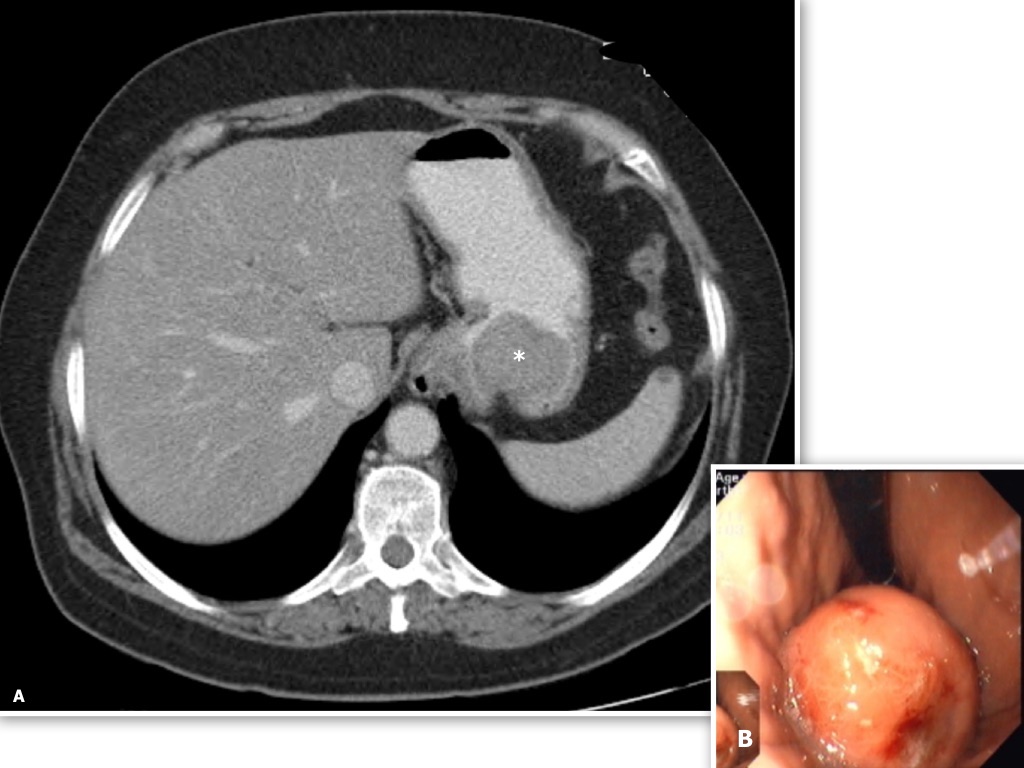

Gastric cardia radiology. Diagnostic centers of america dca is a leading diagnostic imaging facility offering a full array of imaging services in palm beach county florida. We have five state of the art radiology imaging centers in boca raton boynton beach delray beach and wellington florida. The gastric cardia is characterized on barium stud ies by three or four stellate folds that radiate to a central point at the gastro esophageal junction also known as the cardiac rosette fig 2 12. Variations and benign influences may closely resemble the more dangerous lesion.

A healthier weight from surgery can help improve or resolve many obesity related conditions such as type 2 diabetes high blood pressure joint pain heart disease and more. Medically treated small gastric ulcer. Left and right gastric veins drain to portal vein. Ugis has a 70 90 detection rate.

Cain jc jordan gl jr comfort mw gray hk. J am med assoc. The gas tric fundus is dened as the portion of the stomach craniad to the gastric car dia. Commonly accompanying this are abnormally dilated short gastric veins which pass from the splenic vein to encircle the gastric fundus and form gastric fundal varices.